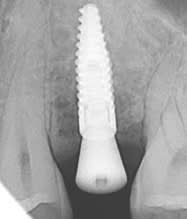

Sur cette radiographie, on voit une « souffrance » de l’os crestal

Un echec suite à la pose de cet implant en 25 en 09.2019.